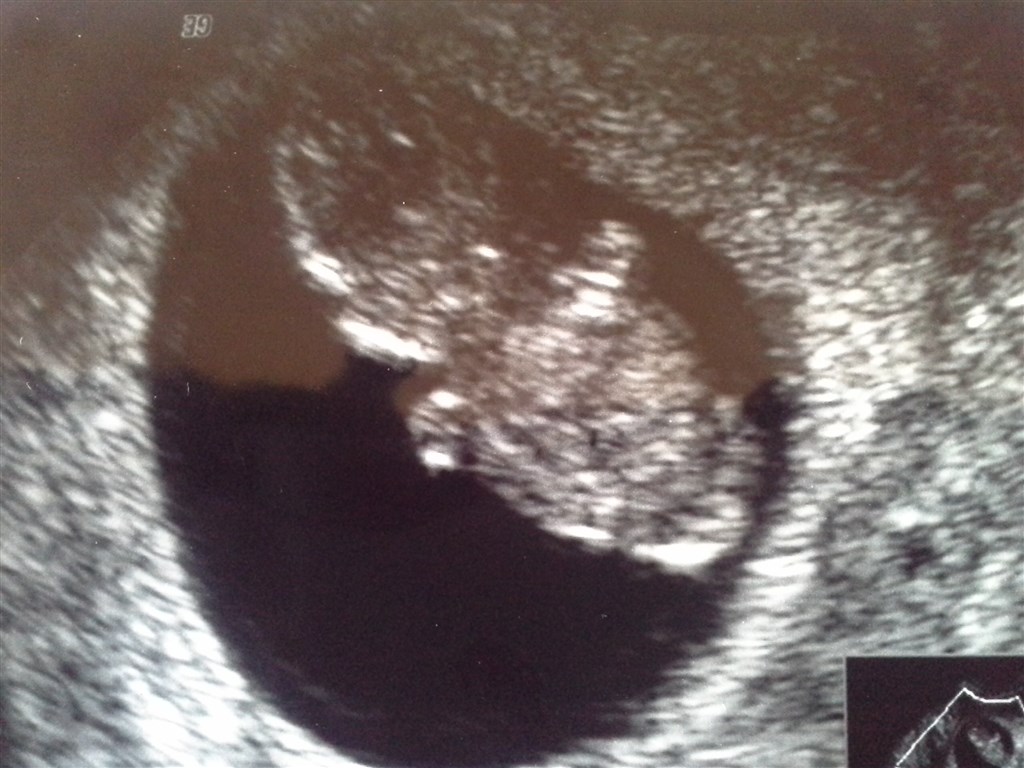

vores lille baby

Elling <3<3

Vedhæftede fotos (klik for at se i fuld størrelse)

Fin bæbs.. Hvor langt er du på billederne?

I følge skanningen 8+5

Vildt at man kan se så meget, det er jo ret tydeligt

Var også helt overrasket. Man kunne se den tog sine små hænder op til hovedet og alt muligt

Det var så stort